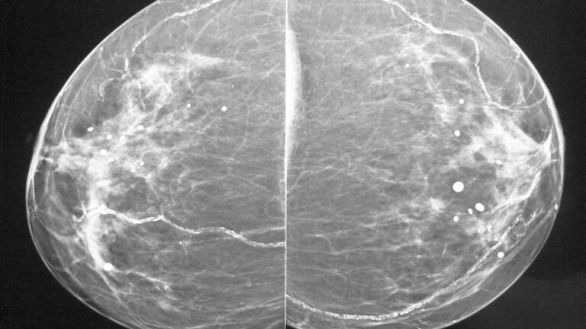

La mamografía detecta también enfermedad cardíaca

(Foto: CC BY-SA 4.0/Sciardullo)

La calcificación arterial mamaria, un hallazgo incidental en la mamografía, ha surgido como biomarcador específico según el sexo para la enfermedad cardiovascular aterosclerótica, que ofrece el potencial de una estratificación de riesgo personalizada. Este avance biomédico lo protagoniza un equipo de científicos y clínicos de EE UU.

La calcificación arterial mamaria; esto es, la acumulación de calcio en las arterias de la mama, que históricamente se ha considerado un hallazgo incidental en la mamografía, ha surgido como un biomarcador específico según el sexo para la enfermedad cardiovascular aterosclerótica (ASCVD) que ofrece el potencial de una estratificación de riesgo personalizada.